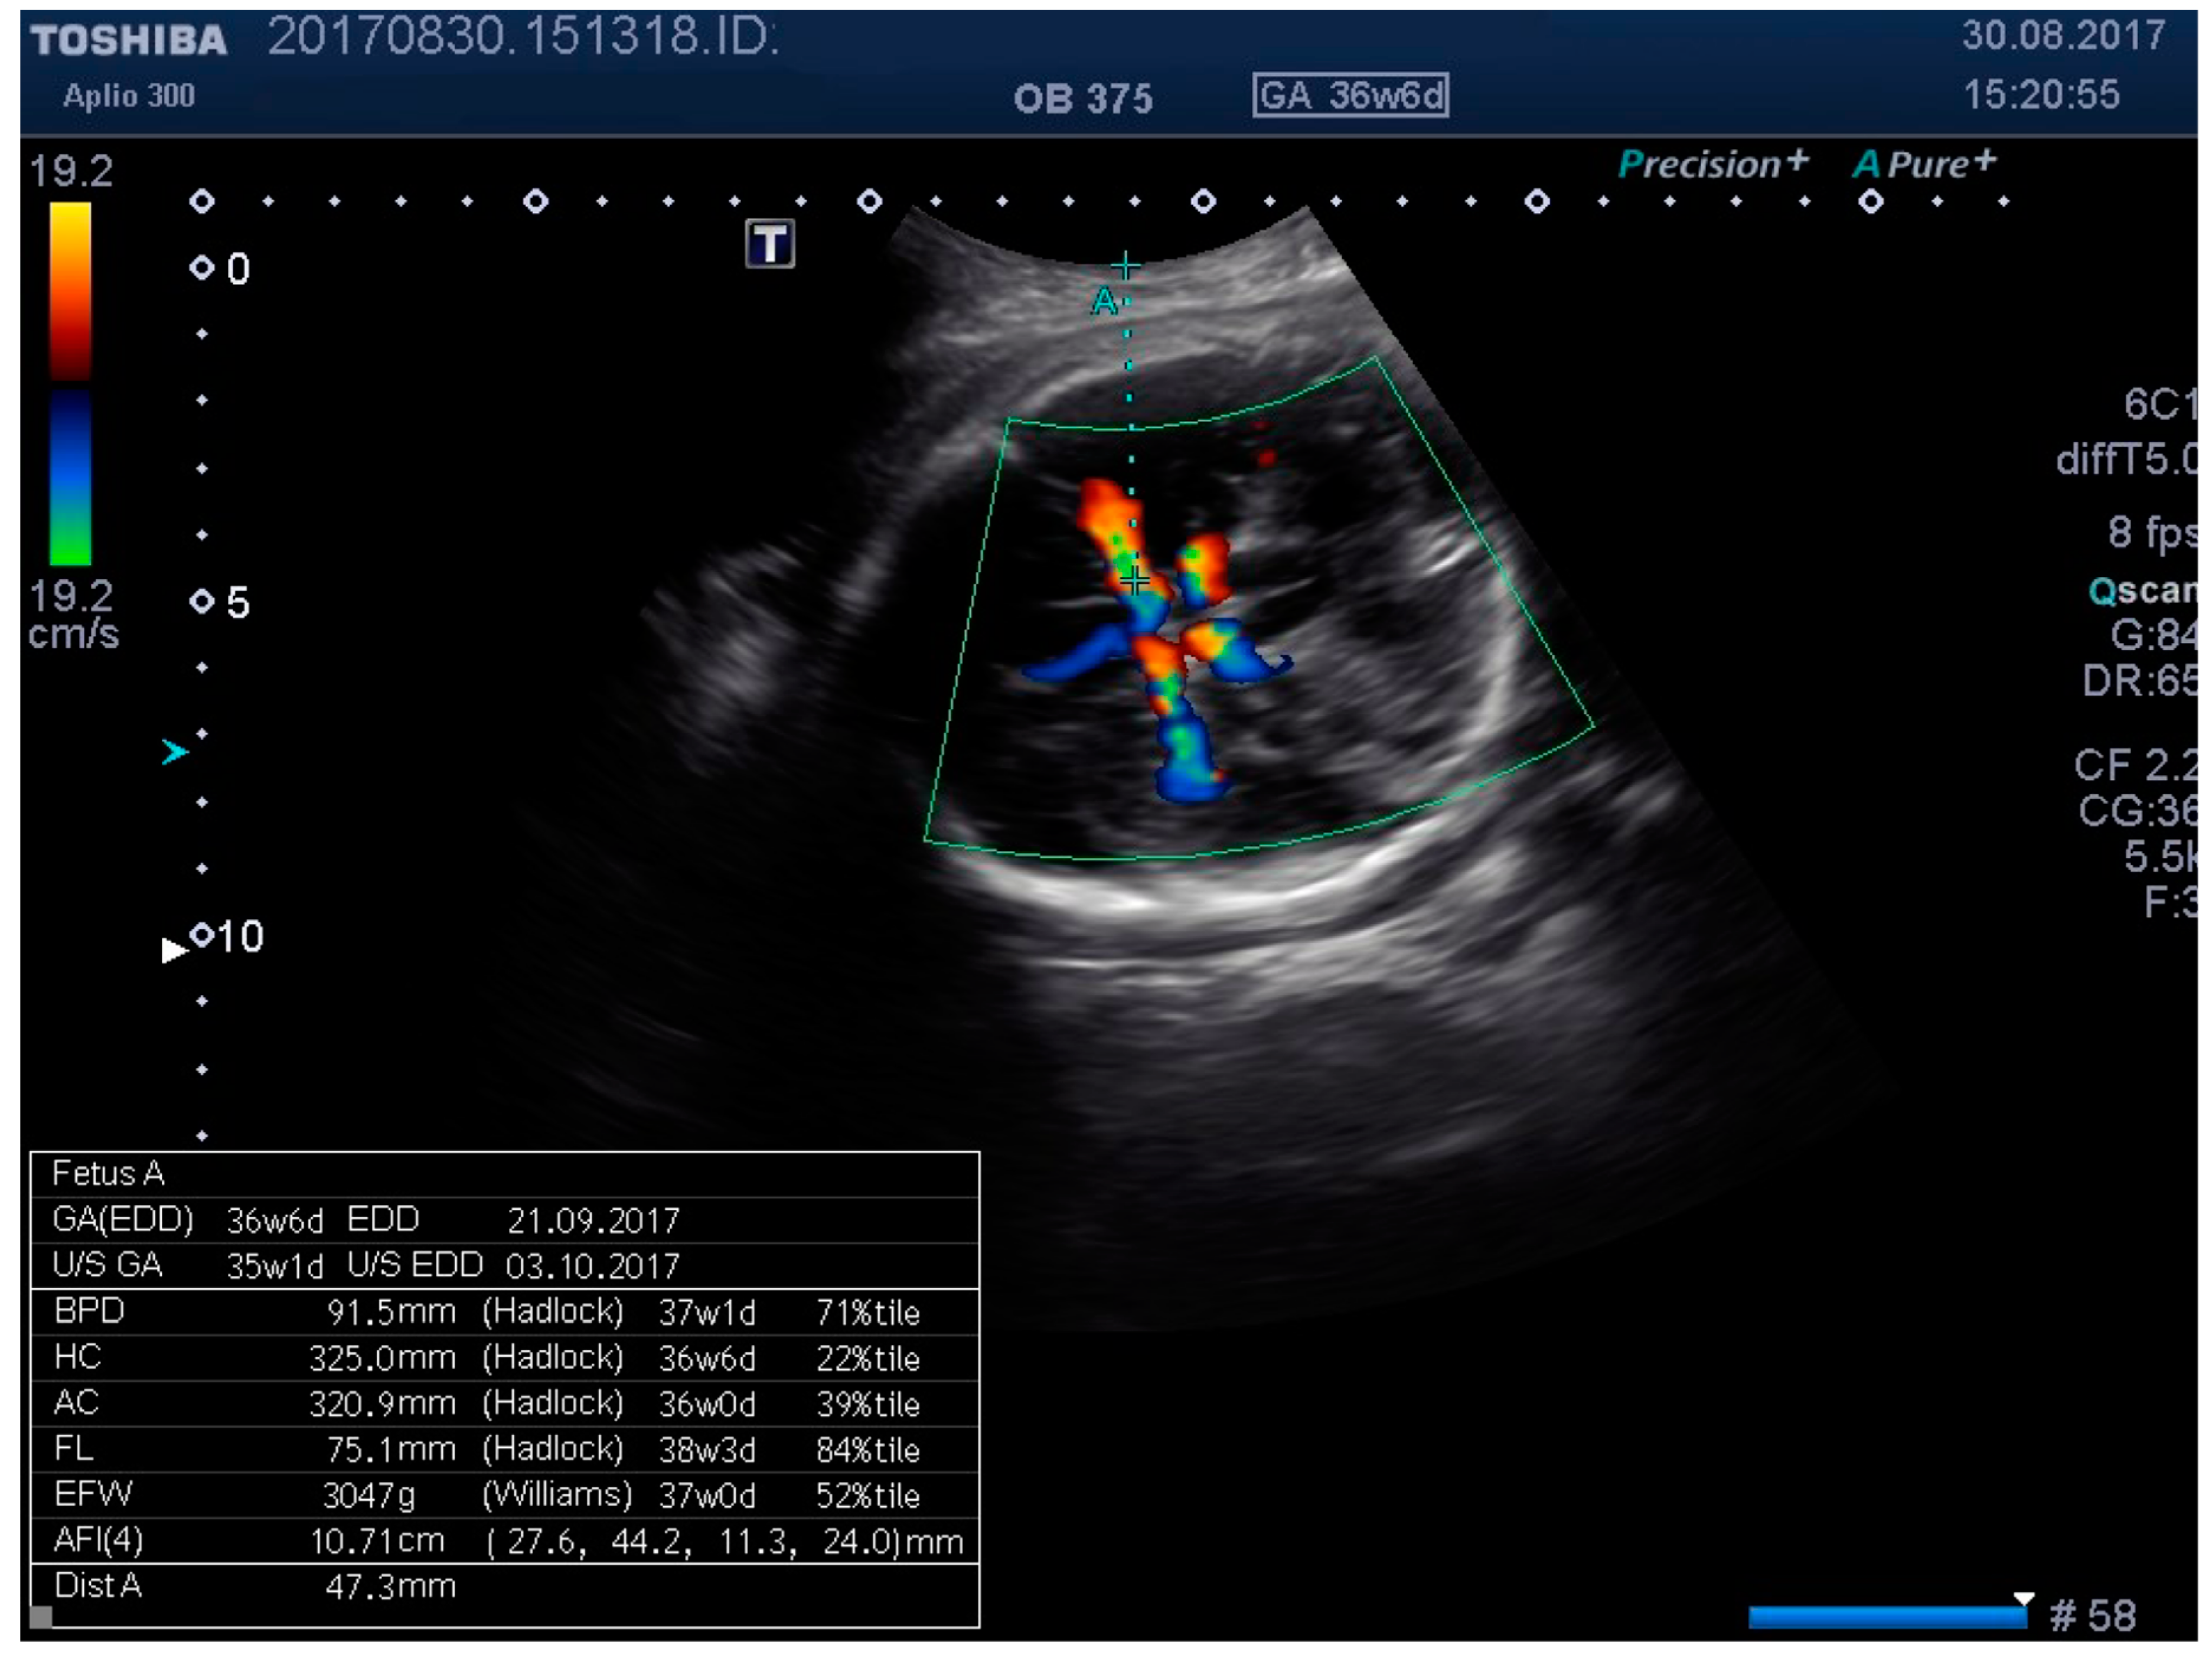

Figure 4. Middle cerebral artery (MCA) identification and measuring the distance to vessel.